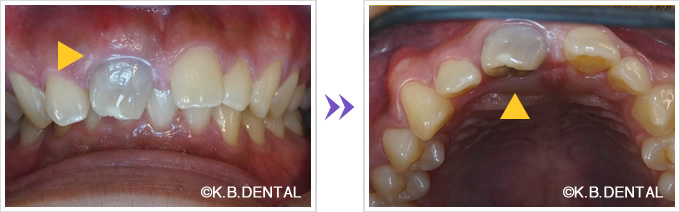

歯牙腫摘出 症例2+埋伏歯(まいふくし)

歯牙腫摘出と埋伏歯抜歯のコンビネーション症例です。お口の違和感で来院された20代女性の方です。抜歯、摘出はピエゾサージェリーを併用するので周囲の歯にダメージを与えず摘出可能、低侵襲に行えます。

通院回数事前検査から手術~抜糸~消毒などを含めて5回、治療期間は約1ヶ月でした。静脈内鎮静法による無痛リラクゼーション麻酔を行い、無痛下で行いました。

料金

静脈内鎮静法による麻酔代込み:約15~20万円(保険適用外)